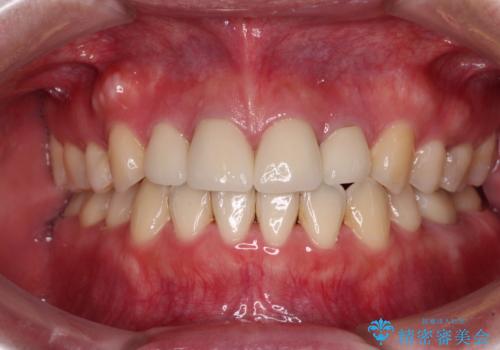

- 口元の突出感と口の閉じにくさを気にして来院された患者様です。

上下左右第一小臼歯4本を抜歯し、ワイヤー装置にて口元を引っ込めるよう矯正治療を行うこととしました。

ご友人などがびっくりするほど口元の突出感を改善することができ、患者様には大変満足していただきました。